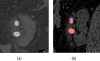

Materials and methods: This Health Insurance Portability Act-compliant study was approved by our institutional review board. Two high-spatial-resolution scan modes (Sharp and UHR) were evaluated using phantoms to quantify spatial resolution and image noise, and results were compared with the standard mode (Macro). Patients were scanned using a conventional energy-integrating detector scanner and the photon-counting detector scanner using the same radiation dose. In first patient images, anatomic details were qualitatively evaluated to demonstrate potential clinical impact.

Results: Sharp and UHR modes had a 69% and 87% improvement in in-plane spatial resolution, respectively, compared with Macro mode (10% modulation-translation-function values of 16.05, 17.69, and 9.48 lp/cm, respectively). The cutoff spatial frequency of the UHR mode (32.4 lp/cm) corresponded to a limiting spatial resolution of 150 μm. The full-width-at-half-maximum values of the section sensitivity profiles were 0.41, 0.44, and 0.67 mm for the thinnest image thickness for each mode (0.25, 0.25, and 0.5 mm, respectively). At the same in-plane spatial resolution, Sharp and UHR images had up to 15% lower noise than Macro images. Patient images acquired in Sharp mode demonstrated better delineation of fine anatomic structures compared with Macro mode images.

Conclusions: Phantom studies demonstrated superior resolution and noise properties for the Sharp and UHR modes relative to the standard Macro mode and patient images demonstrated the potential benefit of these scan modes for clinical practice.